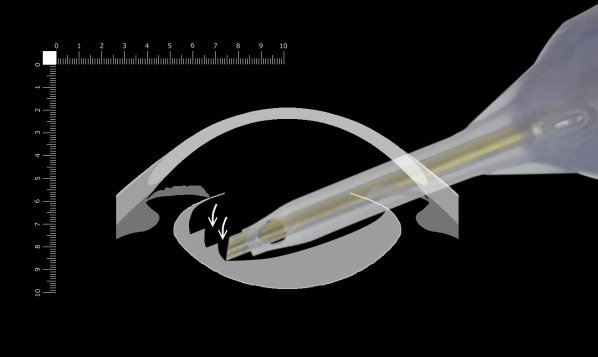

ここでは側面画像から考えます。

溝を少しでも深く掘って底を薄くした方が割れやすいことは間違いありません。深く溝を掘る場合のリスクはパンチアウトです。吸引圧は可能なかぎり下げておきます。(ただし0はおすすめできません)その上でパンチアウトが起こりにくい場所を掘ります。パンチアウトはチップが後嚢に触れただけでは起こりません。(チップ先端の形はリング状です)破嚢が起こるのはチップの先端が後嚢で閉塞された状態で超音波を発振したときです。チップ先端が後嚢で閉塞されにくい場所はどこでしょうか。

手術顕微鏡で眼内を見るとき、ほとんど立体視はできないと言われています。一番深い辺りでは掘っている深さがよく分からなくなることがあります。チップのベベルが垂直より向こう(下)を向いている場合、実際に掘っているところは見えません。そして突き抜けると破嚢してしまうことがあります。

もう少し下方を考えます。ベベルは垂直なので掘っているところは辛うじて見えます。ここもまだ突き抜けて破嚢する危険があります。

さらに先を見てみます。フェイコチップのベベルが垂直より手前(上)を向いている場所では掘っているところがよく見えます。チップの先端を見ながら掘っている限り大きく突き抜けることを回避できます。少し突き抜けたとしてもチン氏帯で固定されているため嚢がチップを閉塞することはありません。ここを深く掘るべきと考えます。